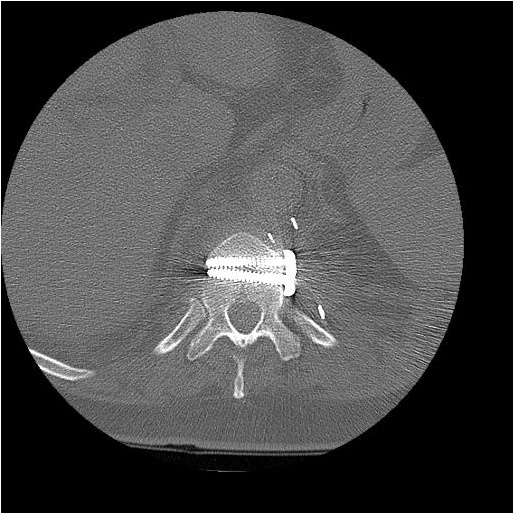

After completion of the spinal procedure, reorientation of the thoracic surgeon by the spinal surgeon is performed, including visualization of the implanted hardware and an explanation of the procedure that was performed (Figures 9a-c). Hemostasis is secured, the chest irrigated, and the posterior mediastinum is inspected for lymph leak (the presence of a CSF leak must be ruled out by the spine surgeon prior to this point in the operation). The diaphragm, if mobilized, is reattached to the fascia of the posterior chest wall with interrupted horizontal 0 prolene sutures or is anchored around the rib. A 28 Fr chest tube is placed in the posterior mediastinum and the chest is closed in a standard fashion. Postoperative spine imaging is necessary to demonstrate adequate position of the hardware and correction of the vertebral defect (Figures 10a-e, Video).

| Figure 10a-e: CT of spine after fixation | Figure 10b | Figure 10c |

| Figure 10d | Figure 10e |